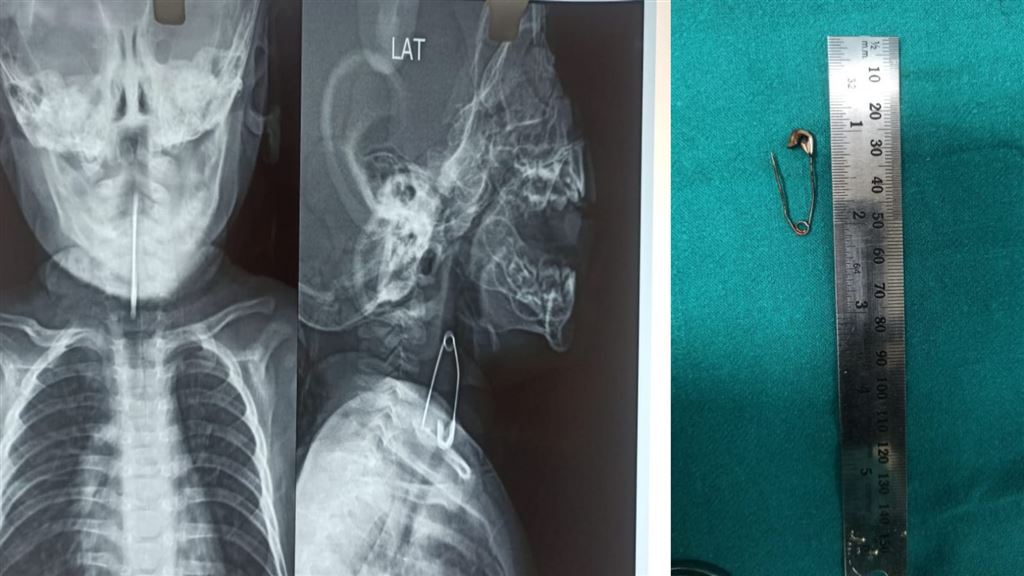

Calcutta Medical College: পাঁচ মাসের শিশুর শ্বাসনালীর কাছে আটকে ছিল মুখ খোলা সেফটিপিন, নিয়ে আসা হল কলকাতা মেডিক্যাল কলে...